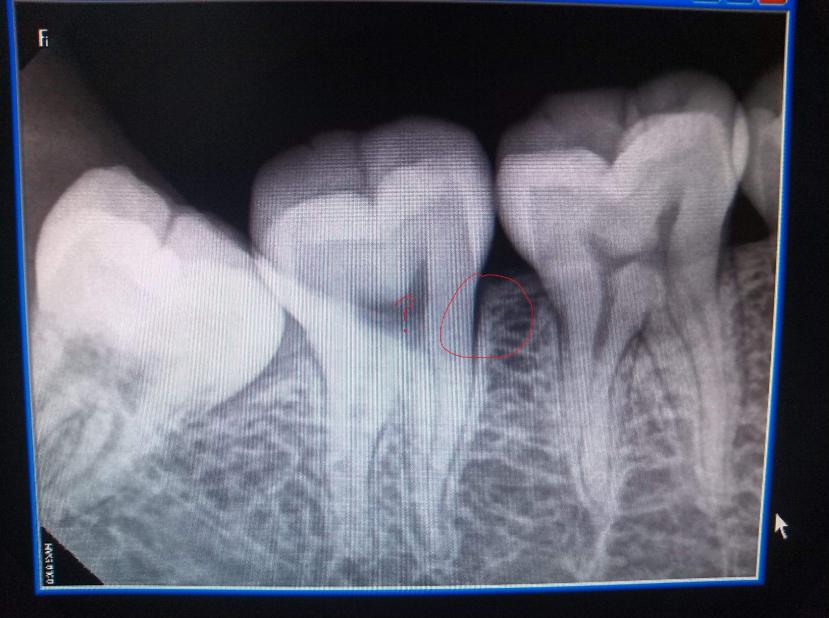

二、拔牙不需要拍片子

很多埋伏牙长在我们的牙龈下面,为了避免损伤神经以及对牙齿拔出难度的估计,我们都需要拍一个片子来保险。

不只是智齿需要拍片子,有的牙齿生长的位置很特别,我们也需要拍片子来进行定位。